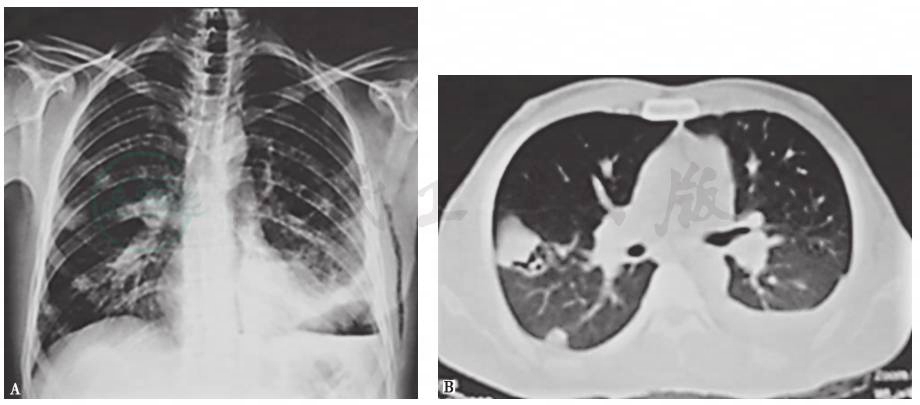

血管炎、系统性红斑狼疮、白塞病等疾病进展累及肺部时,患者可出现发热、咯血等症状,肺内可出现多灶、多形态病灶。其中,白塞病是一种可累及全身的血管炎性疾病,最常见的表现为反复口腔溃疡、生殖器溃疡和虹膜炎,肺部表现包括肺动脉瘤、肺动脉栓塞、肺部结节(图6)、磨玻璃影、胸膜肥厚、胸腔积液、淋巴结增大、肺气肿或肺大疱。本例患者有白塞病家族史,故应警惕该病。

图6 白塞病胸部影像学表现

男性患者,32岁,主因发热、咳嗽、咯血、体重下降2个月入院;反复出现口腔溃疡、生殖器溃疡、下肢结节性红斑,皮肤针刺试验阳性;肺部实变活检提示出血、机化性血栓、血管增生。胸部X线片可见双肺多发斑片影伴左侧胸腔积液(A);胸部CT提示双肺多发结节、实变,左侧胸腔积液(B)。诊断为白塞病

引自:主编:.呼吸系统疑难病例诊疗辨析.第1版.ISBN:978-7-117-26415-0